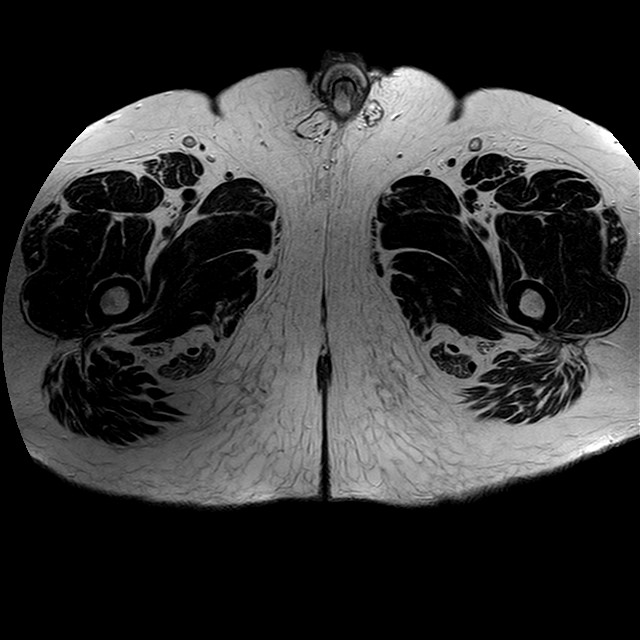

Esami: RMN BACINO

eT2w TSE

Evidenti e simmetriche alterazioni osteofitosiche in regione coxo femorale con riduzione delle rime articolari. Degenerazione completa del cercine glenoideo. Non attuali segni di versamento articolare. Non segni di edema osseo che escludono attuale algodistrofia od osteonecrosi. Lieve e simmetrica riduzione del trofismo della muscolatura glutea.